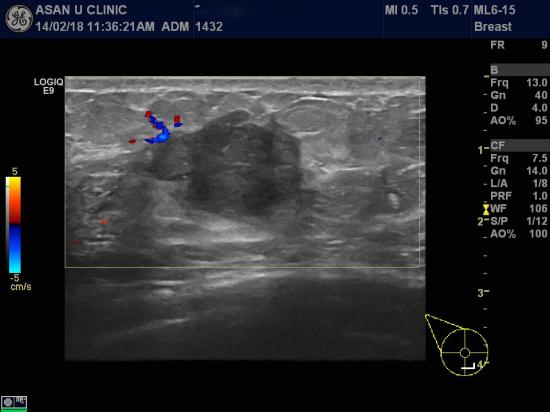

본원에서 시행한 유방 초음파상

우측 유방 6시방향에 유두에서 6cm거리에 2.54cm의 결절,

우측 유방 6시방향에 유두에서 4cm거리에 0.73cm의 결절,

우측 겨드랑이 림프절비대 소견있어 각각